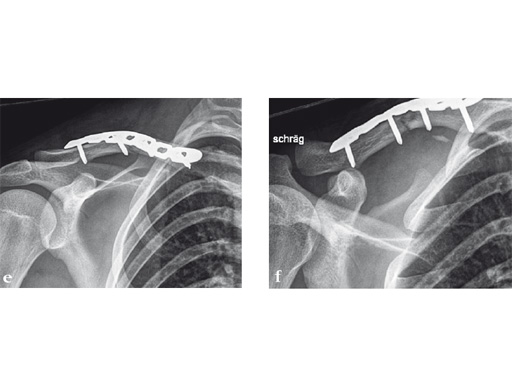

Case 2: a 29-year-old man sustained a midshaft clavicle fracture while playing soccer.

Case provided by Norbert Sdkamp and Martin Jaeger, Freiburg, Germany